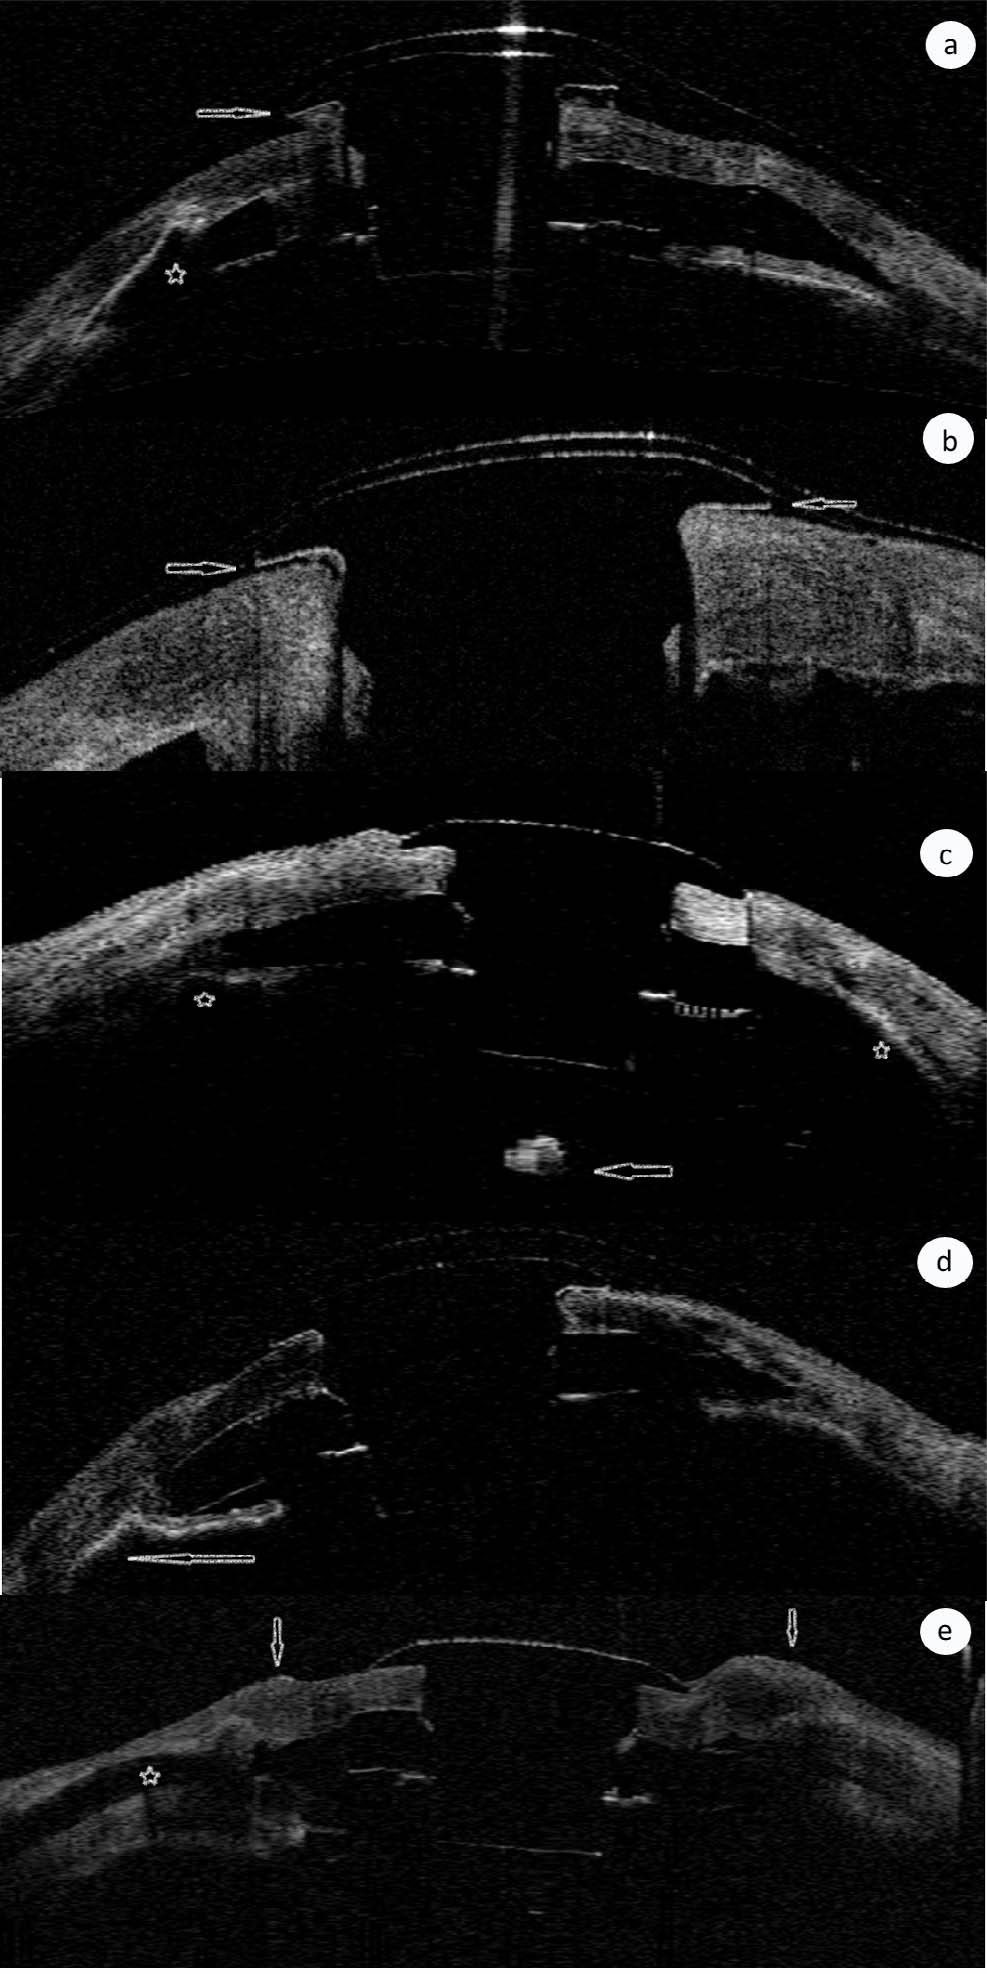

Fig. 1